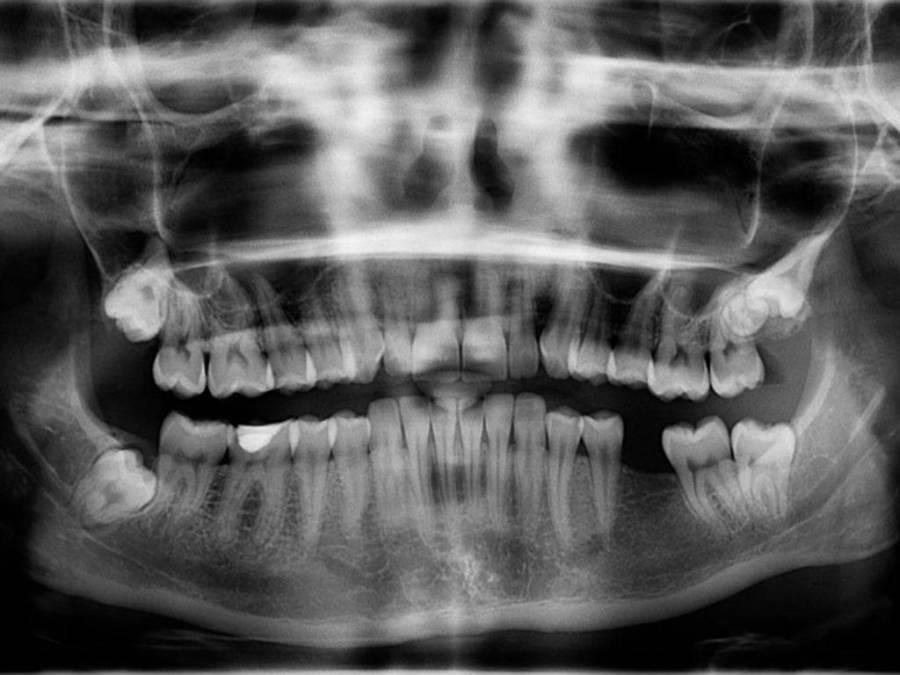

Meningitis bacteriana fue el diagnóstico de los médicos del Hospital del Sur en torno a la muerte de Cristina Elizabeth Lagos, quien acudió al Hospital General del Sur debido a un molesto dolor de muela. A continuación le explicamos de qué trata esta enfermedad y cómo prevenirla.

Tras conocerse que Cristina Lagos llegó por una extracción de muela y cayó en coma, se acusó a los médicos del Hospital General del Sur por negligencia médica y mala praxis. Sin embargo, las autoridades de ese centro regional aseguraron que la fémina presentaba un caso de meningitis bacteriana.

De acuerdo a declaraciones de su madre, Cristiana Lagos presentaba un dolor de muela, tras complicaciones en su caso, cayó en coma y se produjo su muerte. Además se confirmó que padecía enfermedades de base que complicaron su condición médica, de acuerdo a la opinión de los expertos.

Según la doctora en Medicina y Cirugía, Cesia Figueroa consultada por EL HERALDO, en el caso de la paciente era necesario hacerle exámenes previos antes de realizarse la extracción de muela ya que presentaba otras comorbilidades según diagnóstico.

”Si estaba hipertensa, el dolor pudo causarle el accidente cerebrovascular” mencionó la profesional de la salud, descartando una simple “extracción de muela” y atribuyendo a la gravedad de la meningitis bacterial en la muerte de la hondureña.